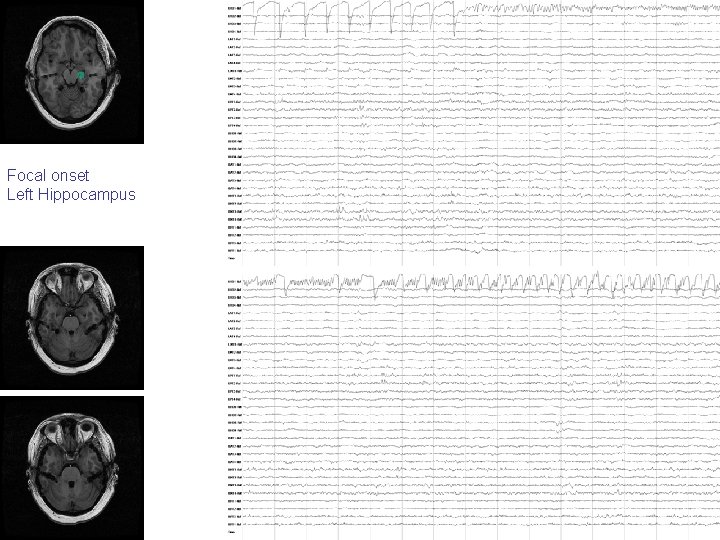

Focal onset Left Hippocampus

Regional onset Left Hippocampus Parahippocampus

Regional onset Right Uncus Hippocampus

Regional onset Right Uncus Hippocampus “spread” to Generalized